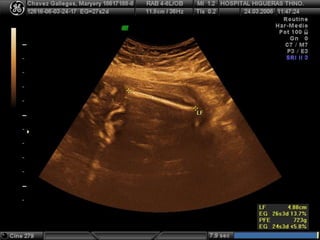

ESQUELETO

LONGITUD DE FÉMUR

LO MÁS IMPORTANTE

(cálculo peso,

estimación talla fetal

y EG  2º trimestre)

VER TAMAÑO Y

FORMA